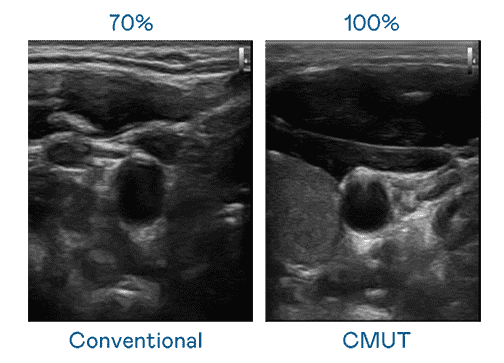

CMUT 技术是一种用电容式微机电元件来产生超音波讯号的技术。。。。与传统 PZT 压电式技术相比,,CMUT 频宽增加 30%,,,,更宽频的超音波讯号让影像解析度大幅提升,,,是实现高影像品质医疗超音波扫描、、、、促进精准医疗发展的关键技术。。

大频宽带来超清晰影像

超音波影像的解析度高低,,首先取决于探头能发出的讯号频宽。。。尊龙集团 CMUT 可提供高清晰的超音波讯号,,,提供高频宽、、高灵敏度、、、、影像纹理细节更高的超音波影像,,,,协助医护人员缩短影像判读时间及利用精准的医疗影像进行诊断。。